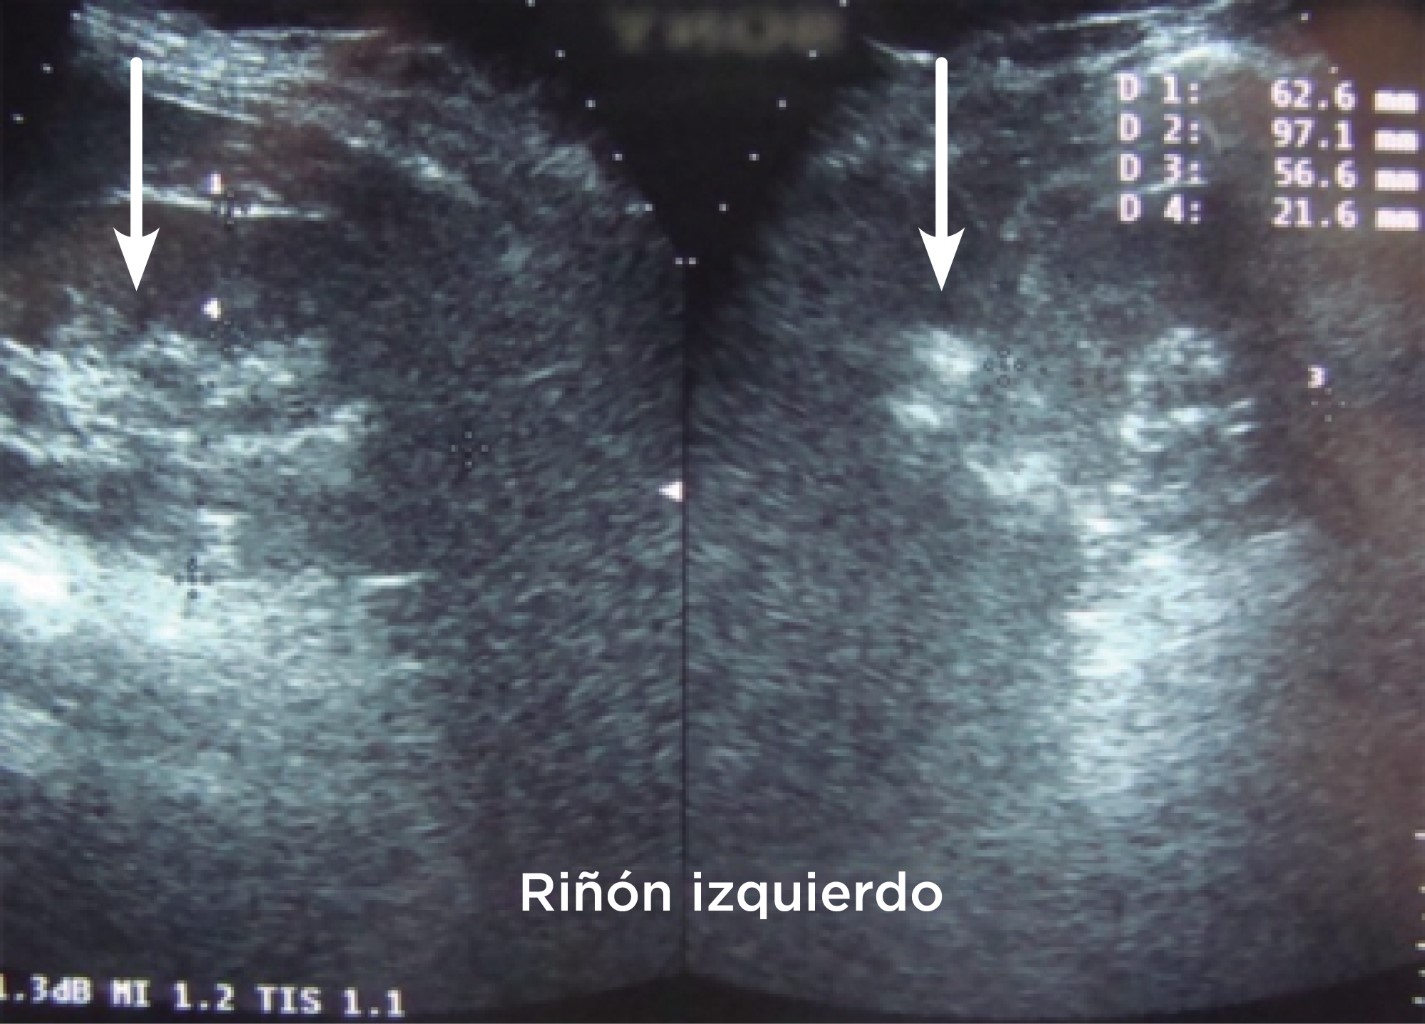

Lactante femenino que acude por vez primera al Servicio de Urgencias cuando tenía un mes de edad (5 de octubre de 2012) por la presencia de vómito, para lo cual se le indica tratamiento para reflujo gastroesofágico y es enviada a casa sin mejoría. A los 10 días llega nuevamente a Urgencias por vómito, fiebre, pérdida de peso y deshidratación, se ingresa con el diagnóstico de probable enfermedad hipertrófica del píloro infantil e infección de vías urinarias. Clínicamente no tiene incremento de peso (3.3 kg) y talla (50 cm). Durante su estancia le realizan exámenes de laboratorio y gabinete (Figuras 3 y 4, Tabla 4).

Como hallazgo se reporta nefrocalcinosis en ambas siluetas renales y se enfoca el diagnóstico a una tubulopatía, específicamente acidosis tubular renal distal, iniciando la terapia alcalina junto con un suplemento de potasio vía oral.

Figura 3

Figura 4